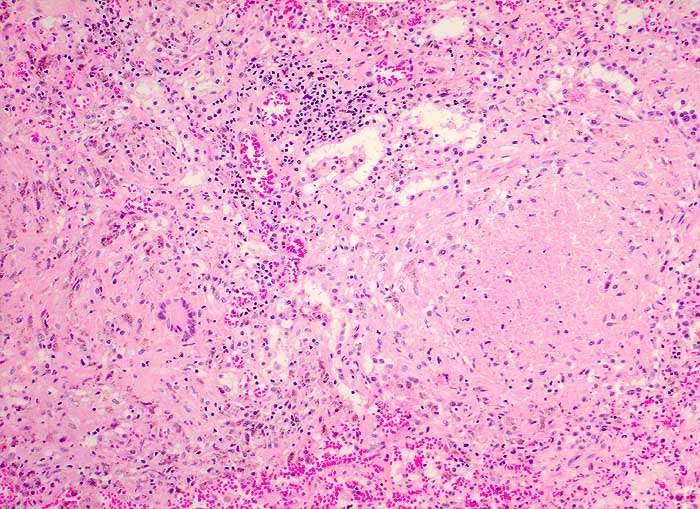

p/ Tuberkulöse Lymphadenitis

Tuberkulöse Lymphadenitis

Die meist atrophischen Epitheloidzellen sind oft nur schwer von Venulenendothelien unterscheidbar und sind nur relativ selten zu deutlich erkennbaren Granulomen zusammengeballt. Bei Vorliegen von verkäsenden Granulomen erscheint der Ausstrich feinkörnig-detritisch. Eine granulozytäre Entzündung muss bei AIDS Patienten an eine Tuberkulose denken lassen.